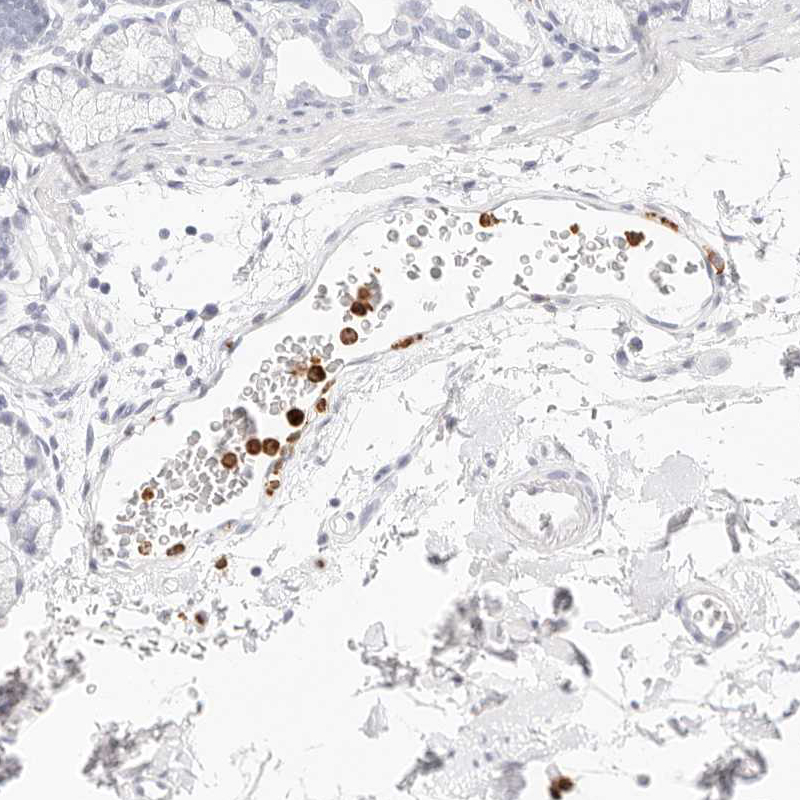

Immunohistochemistry analysis in human bone marrow and cerebral cortex tissues using HPA029874 antibody. Corresponding CAMP RNA-seq data are presented for the same tissues.